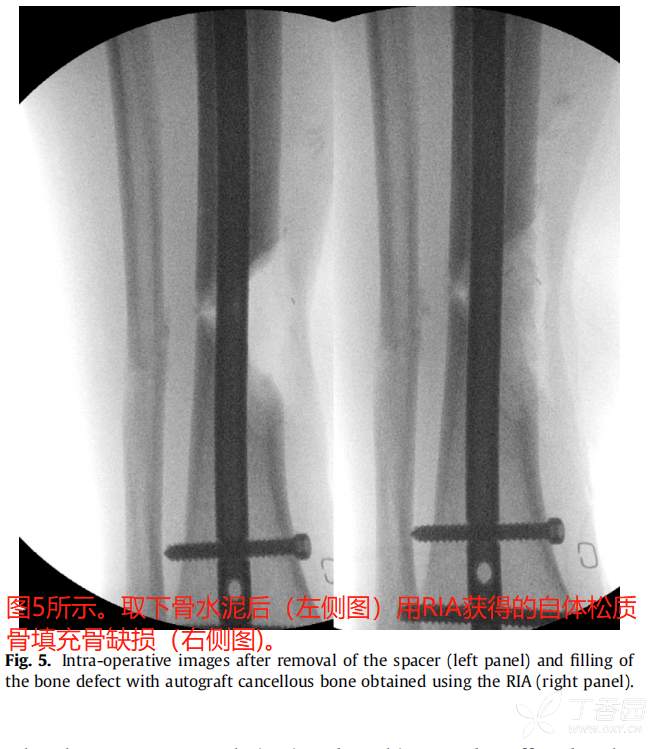

最近,国外采用Reamer灌洗吸引器系统(RIA, Depuy Synthes, West Chester, PA)从股骨髓腔进行扩孔已经成为一种常见的松质移植物来源。

在一些研究中,RIA技术的结果与更传统的髂骨移植进行了比较。Belthur等报道使用RIA后愈合率为90%,而髂骨移植后愈合率为80%。【5】此外,在本研究中,RIA组的疼痛评分较低,但髂嵴骨移植物摘除术后并发症发生率较高。

典型病例: